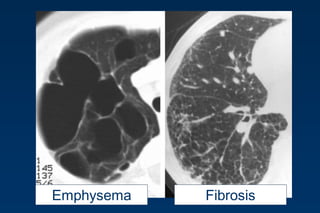

Emphysema

histopathological definition

…..permanent abnormal enlargement of airspaces

distal to the bronchioles terminales and

…...destruction of the walls of the involved

airspaces

Emphysema typically presents as

areas of low attenuation without

visible walls as a result of

parenchymal destruction.

HONEYCOMBING

Defined as - small cystic spaces with irregularly

thickened walls composed of fibrous tissue.

Predominate in the peripheral and subpleural

lung regions

Subpleural honeycomb cysts typically occur in

several contiguous layers. D/D- paraseptal

emphysema in which subpleural cysts usually

occur in a single layer. 62